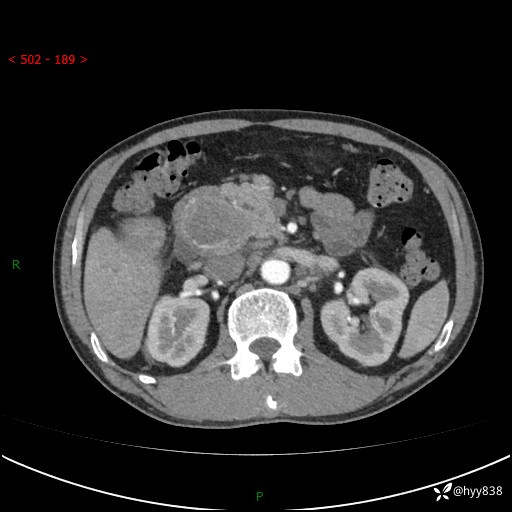

上腹部CT平扫+增强(两期)